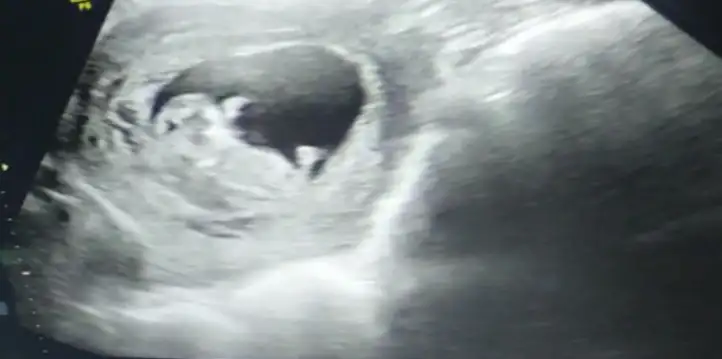

Cinsiyet tahmini yapabilen varmı

• 17134404001124555547007666287492.webp

17134404001124555547007666287492.webp

24,4 KB · Görüntüleme: 79

• 17134404379845450892110518396676.webp

17134404379845450892110518396676.webp

27,2 KB · Görüntüleme: 62